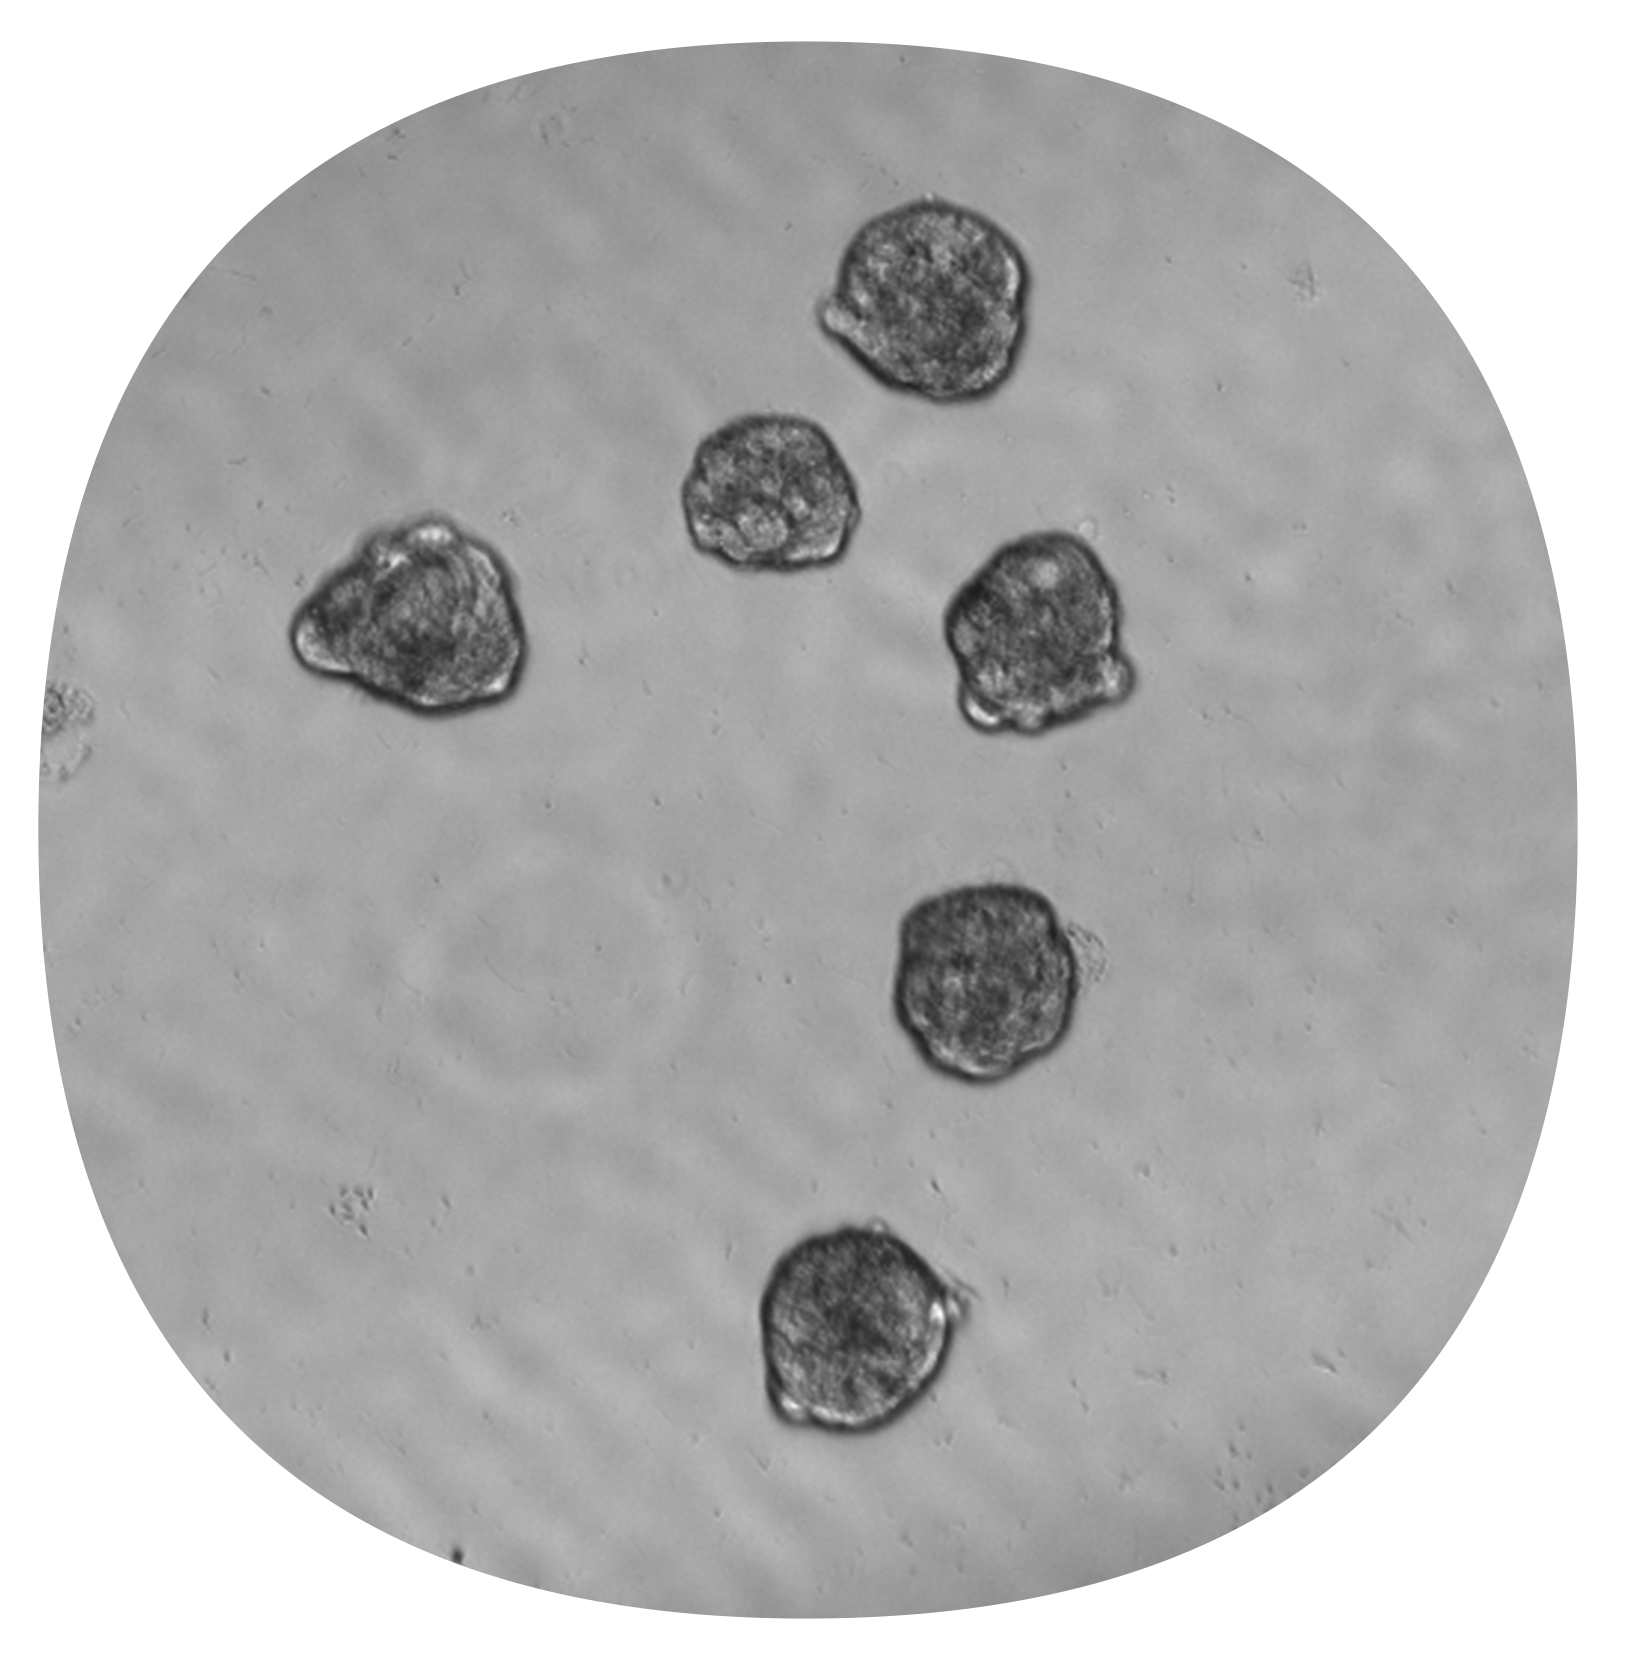

After 48-hour incubation in GrowDex® hydrogel which included a transport from Helsinki to Solna (A), the average diameter of spheroids was 70 μm (B) and the average roundness was 0.72 out of 1 (C).

After Cellbox transport in 384W plates maintained at 37C and 5% CO2 from Helsinki to Solna during a 48-hour incubation in GrowDex® hydrogel (A), the average diameter of spheroids was 70 μm (B) and the average roundness was 0.72 out of 1 (C).

This collaborative effort introduces an innovative approach to efficiently produce miniaturized spheroids, yielding 20,000 spheroids from 0.8 million cells suspended in 100 μL medium in just 3 minutes, with each spheroid measuring approximately 70 μm in diameter.

These spheroids exhibit robustness, homogeneity, and functionality. The incubation of cells in nanoliter-scale droplets promotes cell contact, facilitating cell aggregation and accelerating spheroid formation.